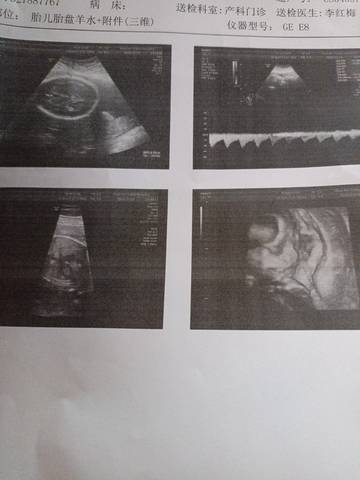

感觉三维做的不是很清楚,下面写的也不多

图片上面来看的话呢,像那种三维检查是一样的,只要上面文字表达一些,我正常就好了

别担心,要保持好的心情,像宝宝的位置动作,都影响回声,正在检测时如果宝宝动了也看不清。没事的。我那时的三维图上,看上去脸上还多长了块肉呢。

其实有些医生他没有写的那么详细的呀,只要他说没有什么问题的话,就不用太担心的哦